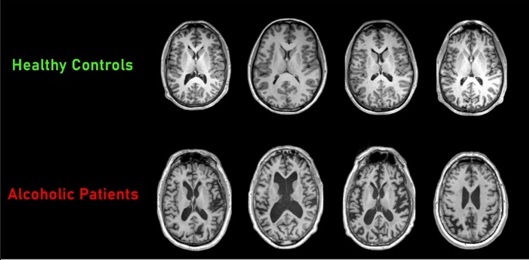

술을 마실 때 일어나는 진짜 일은

우리의 뇌세포가 '마비'된다는 겁니다.

그 순간 뇌세포들은 말 그대로 좀비가 돼요.

그리고 다음 날, 파티가 끝나면

그중 일부는 죽어버립니다.

다시는 정상으로 돌아오지 않죠.